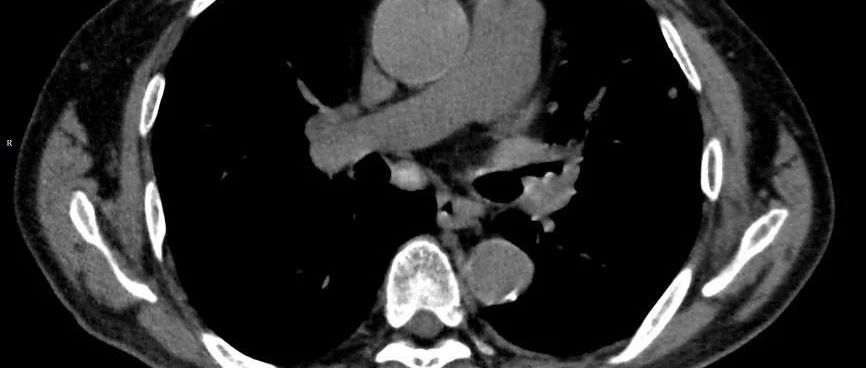

*仅供医学专业人士阅读参考一文搞定,不再误判! 现病史患者闫xx,男性,29岁,以“反复胸腔积液1年余”入院。患者于2020年4月因胸憋、气短就诊于当地市医院,考虑为结核性胸膜炎、右肺结核,给予抗结核治疗(异烟肼0.3g/日、利福平0.45g/日、吡嗪酰胺1.25g/日、乙胺丁醇1g/日)半年余。到2020年12月份复查胸部CT提示右侧胸腔积液较前增多,后来又调整了抗结核方案(异烟肼0.3g/日、利福平0.45g/日、吡嗪酰胺1.5g/日、乙胺丁醇1g/日、左氧氟沙星0.4g/日),一直规律用药,复查也提示右侧胸膜炎和右肺结核有明显好转。...